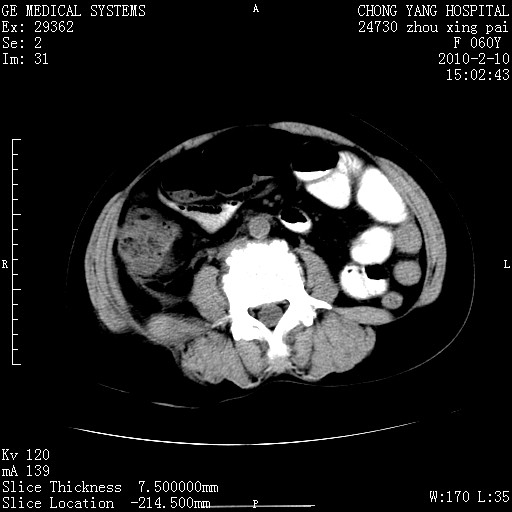

标题: CT24682:F60Y 腹痛 其它不详 [打印本页]

标题: CT24682:F60Y 腹痛 其它不详

1)胆总管末端梗阻,不排除结石所致可能。2)胰腺炎。3)慢性胆囊炎可能。4)左侧输尿管上段扩张。5)少量腹水。6)双侧少量胸腔积液,伴两下肺部分肺萎陷。

1)胆囊炎。2)胆源性胰腺炎。3)右肾周筋膜增厚,肾旁前间隙积液。4)左侧输尿管上段扩张。5)少量腹水。6)双侧少量胸腔积液,伴两下肺部分肺膨胀不全。

1)胆总管末端梗阻。2)胰腺炎。3)慢性胆囊炎可能。4)左侧输尿管上段扩张。5)少量腹水。6)双侧少量胸腔积液,伴两下肺部分肺萎陷。